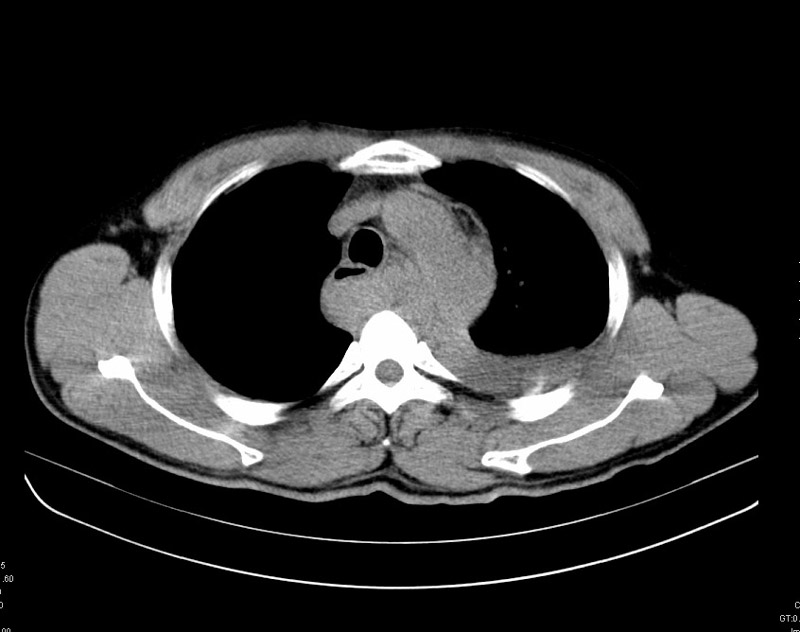

男性,40岁。胸部被车压伤伴胸痛1小时来院就诊。检查:一般情况尚可,血压110/80,胸部及上腹部压痛。结果在三天后公布。骨窗在横断位、冠矢状显示肋骨、胸椎、和胸骨未见骨折征象。

ct11308:胸部外伤1小时(证实病例) (2008-1-13 16:2)结果如下:病人入院后两小时后症状加重,8小时后在征得病人家属同意做了ct增强扫描。如下图。最终临床诊断:外伤性胸主动脉破裂并纵隔内血肿。由于有运动性伪影,胸骨在矢状面重建的图像似有骨折征,这是一种假象,我们称之为“假骨折”,这在多层ct重建中经常性遇到,必要时要结合横断图像鉴别之。现在,病人的一般情况较差,是否要手术家属尚有争议,如果手术修补,难度较大,需要专门预定制作固定支架。

以下是引用拾荒者在2008-1-16 18:46:00的发言:[br]ct11308:胸部外伤1小时(证实病例) (2008-1-13 16:2)结果如下:病人入院后两小时后症状加重,8小时后在征得病人家属同意做了ct增强扫描。如下图。最终临床诊断:外伤性胸主动脉破裂并纵隔内血肿。由于有运动性伪影,胸骨在矢状面重建的图像似有骨折征,这是一种假象,我们称之为“假骨折”,还有双侧肋骨的“假骨折”,这在多层ct重建中经常性遇到,必要时要结合横断图像鉴别之。现在,病人的一般情况较差,是否要手术家属尚有争议,如果手术修补,难度较大,需要专门预定制作固定支架。[br][br]再次表示感谢!

当然,对于该病例,其它非重要的诊断还有:右侧少量气胸;左侧胸腔积液;左侧轻度肺挫裂伤。对于纵隔内血肿,我们曾经遇到过多例,也有怀疑主动脉的破裂,但是,均未得到具体出血部位的明确诊断。